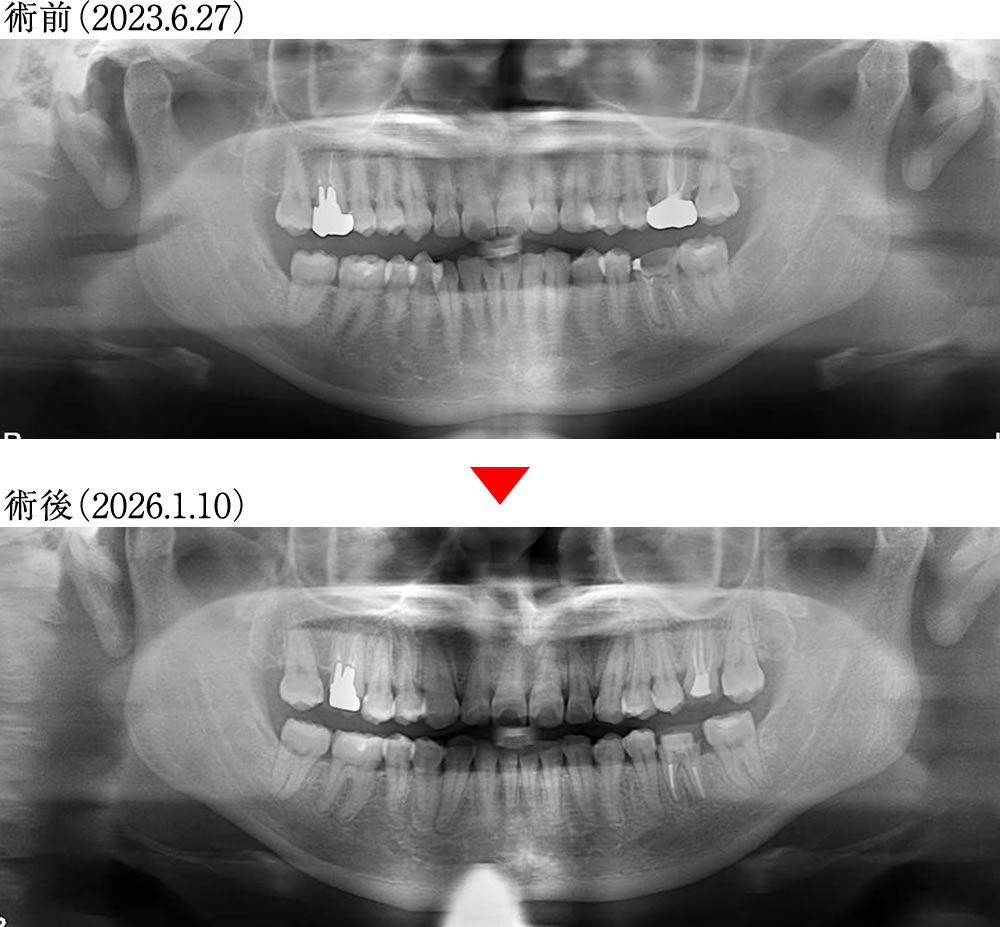

術前術後のレントゲン画像

歯根の吸収も特に見られず、咬合平面は水平に整いました。